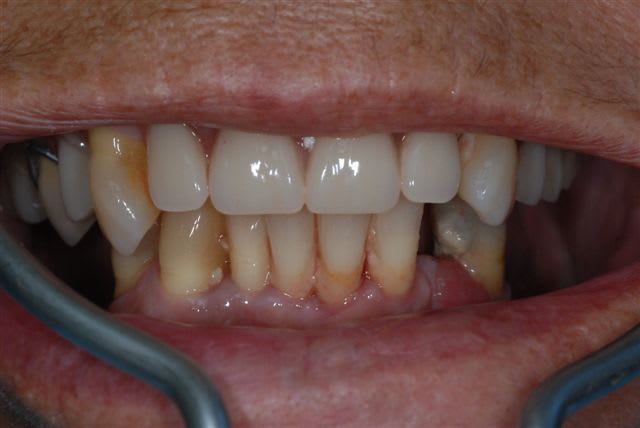

nouveau patient, il en a assez de son complet sup et de son édentation mandibulaire (le stellite est dans un tiroir depuis 15 ans).

Il veut vraiment une solution fixe.

je vous avoue que ce qui me pose le plus problème c'est son occlusion. Sous le complet, à la palpation on ne sent pas une crête très résorbée (mais la palpation est parfois (souvent) trompeuse). Le patient me dit que lorsqu'il avait encore ses dents en haut elles étaient en "bout à bout" avec les incisives inf. Il ne possède pas un profil cutané typique des classes III squelettique. J'ai vérifié s'il ne propulsait pas en fermant: négatif. Il semble donc qu'une résorption centripète progressive ait eu lieu au niveau de son maxillaire aboutissant à l'état actuel. je vais faire une téléradiographie de profil pour préciser la classe squelettique.